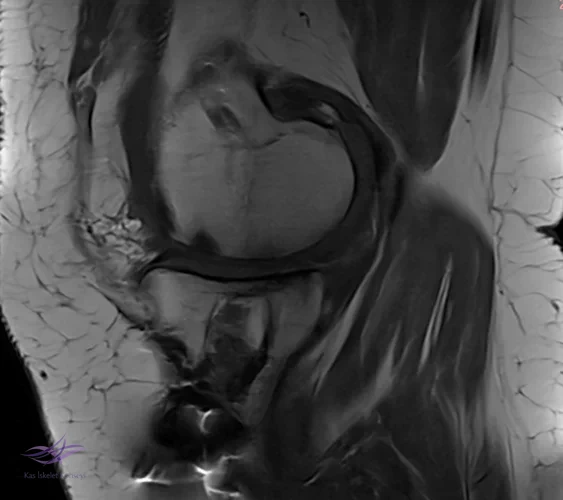

İncelemeler: USG'de minimal suprapatellar efüzyon. MCL heterojen görününde fibrillar yapı bozulmuş. Direkt grafi ve MRG'leri ektedir.

Resim 3. Resim 3. Sagittal MRG.